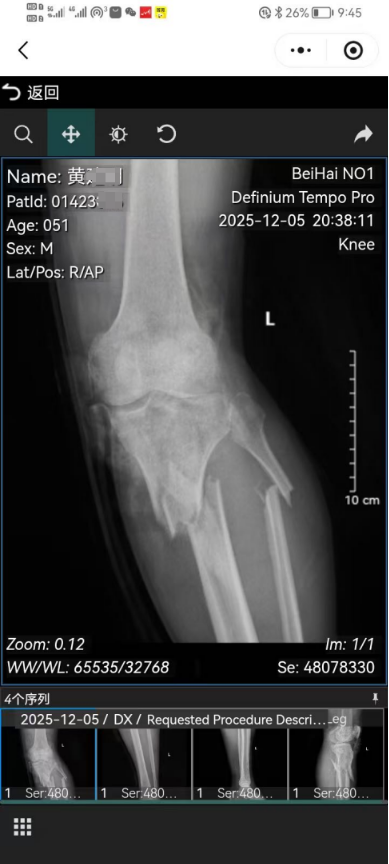

到了医院,先挂号缴费,尴尬的是我们家的卡里余额只有50多元,就等着15号孩爸发工资了。还好,他同事就是老板派来给交费的,交了700多元,很快安排了拍片。在这期间,孩爸的同事一直陪着。一个小时左右,片子结果出来了,医生说,小腿粉碎性骨折,必须做手术,要立刻办理住院,目前没有床位,得等床位,让我去交费。发现同事不在,我在收银台等着,给我父亲打了电话让他转1000元(多了他也没有,都是穷鬼)过来急用一下。父亲的钱还没到,收费员告诉我要交1100元。我在想,实在不行得跟姑子姐她们开口了,但是我心里是极度不愿意的,不想再欠她们的任何人情。就在这时,他同事过来了,把费用交了。我尴尬地给他说:哎呀,不好意思哈,我们这家实在是混得太差了,卡里余额不到百元,实在是尴尬啊!他微笑着说:没事没事!

关于腿部骨折,医生很明确地告诉我们必须手术治疗,只是现在还没有完全消肿,缝合部位也没有愈合,怕造成感染,暂时还无法手术。手术就意味着要打钢钉钢板,未来的风险系数更大且未知,后期费用也很昂贵。我们是想保守治疗,现在就静待结果。